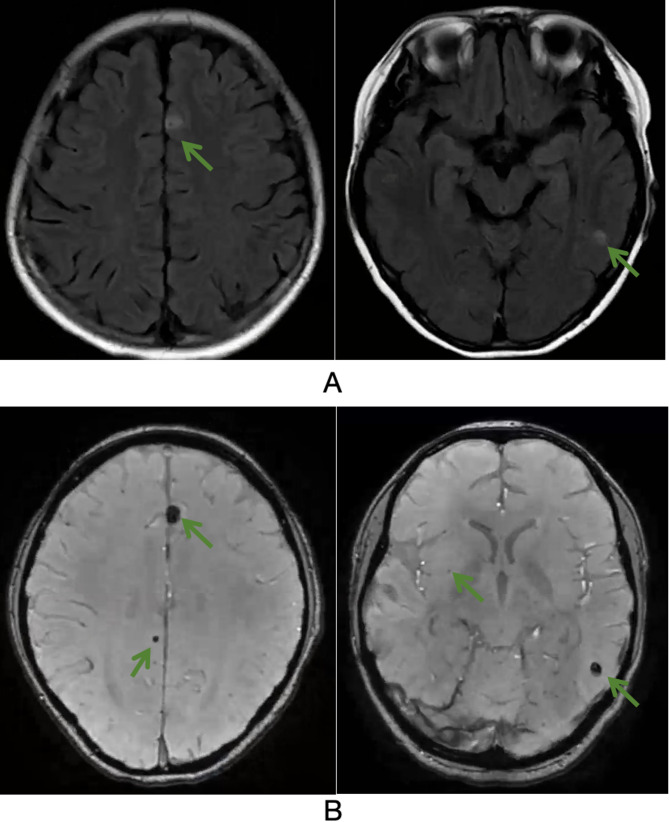

Methods: We report a rare case of ES in a pediatric patient presenting with DAH and intracranial hemorrhagic lesions. Diagnostic evaluations included high-resolution chest CT (HRCT), bronchoscopy, brain MRI, lung biopsy, Positron emission tomography - computed tomography (PET-CT), and biopsy of a mass in the right thigh. Fluorescence in situ hybridization was performed to detect SMARCB1 (INI1) gene deletion.

Results: A 13-year-old male presented with anemia and later developed hemoptysis with a decreased hemoglobin level. HRCT revealed bilateral ground-glass opacities consistent with DAH. Extensive autoimmune and infectious workups were all negative. Brain MRI demonstrated microhemorrhages. Despite corticosteroid therapy, the patient's condition worsened. PET-CT identified a hypermetabolic soft tissue mass in the right thigh, which on histopathological examination was confirmed as INI1-deficient ES. FISH analysis confirmed INI1 deletion.